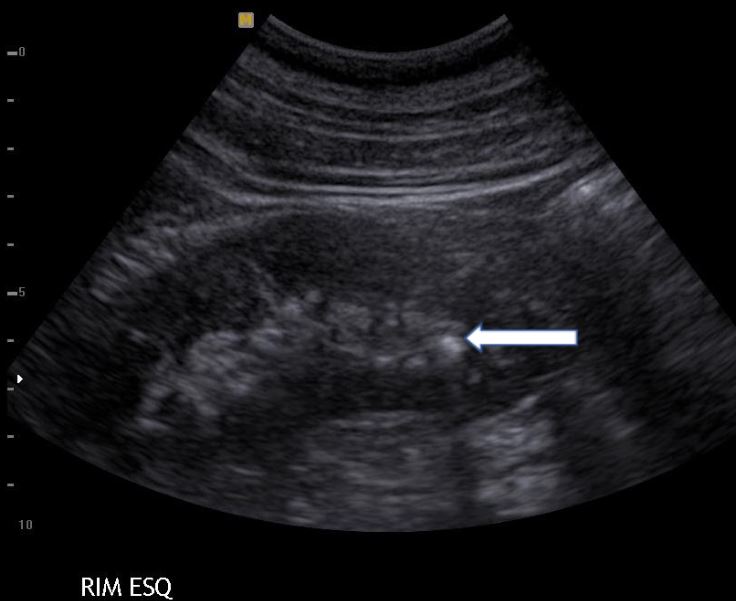

Rim esquerdo com um cálculo no terço inferior, apontado pela seta branca. Exame de ultrassom do abdome total.